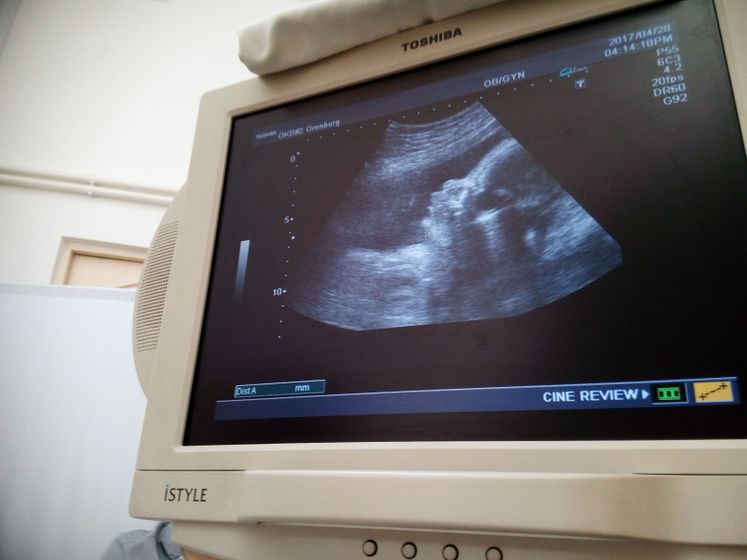

Так была рада увидеть ее после 2 скрина) тогда она показывала попу))) сейчас она даже помохала маме)да правда изжога тревожит перед сном… ночь не ночь))) но энергии ттт, стало больше… но почему то срываться стала, взяла даже валерьянку))) чуть чуть о грустном...( на личном беспорядок( почему некоторые мужчины до сих пор не осазнают

наше положение… или просто не любят( раз позволяют грубости в словах( главное все же, чтобы наши малышки были здоровы) заметила, что на животике уже проглядывается полоска))) так здорово видеть животик все выше и не видеть другую зону)))) всех целуем)